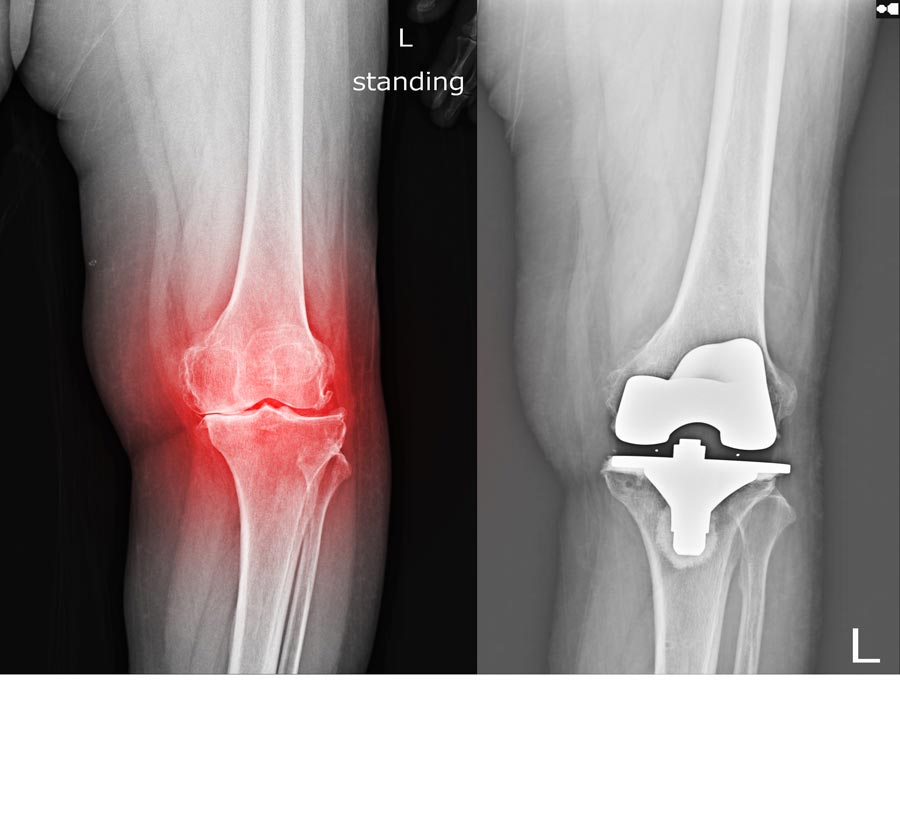

Knee replacement surgeries involve replacing the damaged bone with an artificial one (prosthesis) to relieve the pain and restore the knee functions. Although most of the knee replacement surgeries are successful, it may fail for reasons like high-impact activities, overweight, etc. These may result in break or wear out of the prosthetic causing pain, stiffness or instability and difficulty to perform everyday activities.

When the knee replacement fails, a second surgery may be recommended, which is called knee joint revision surgery.

Knee joint revision is a procedure in which the surgeon removes the previously implanted artificial knee joint that is no longer functioning properly and replaces it with a new implant. The procedure is also known as revision total knee arthroplasty where it also uses bone grafts.